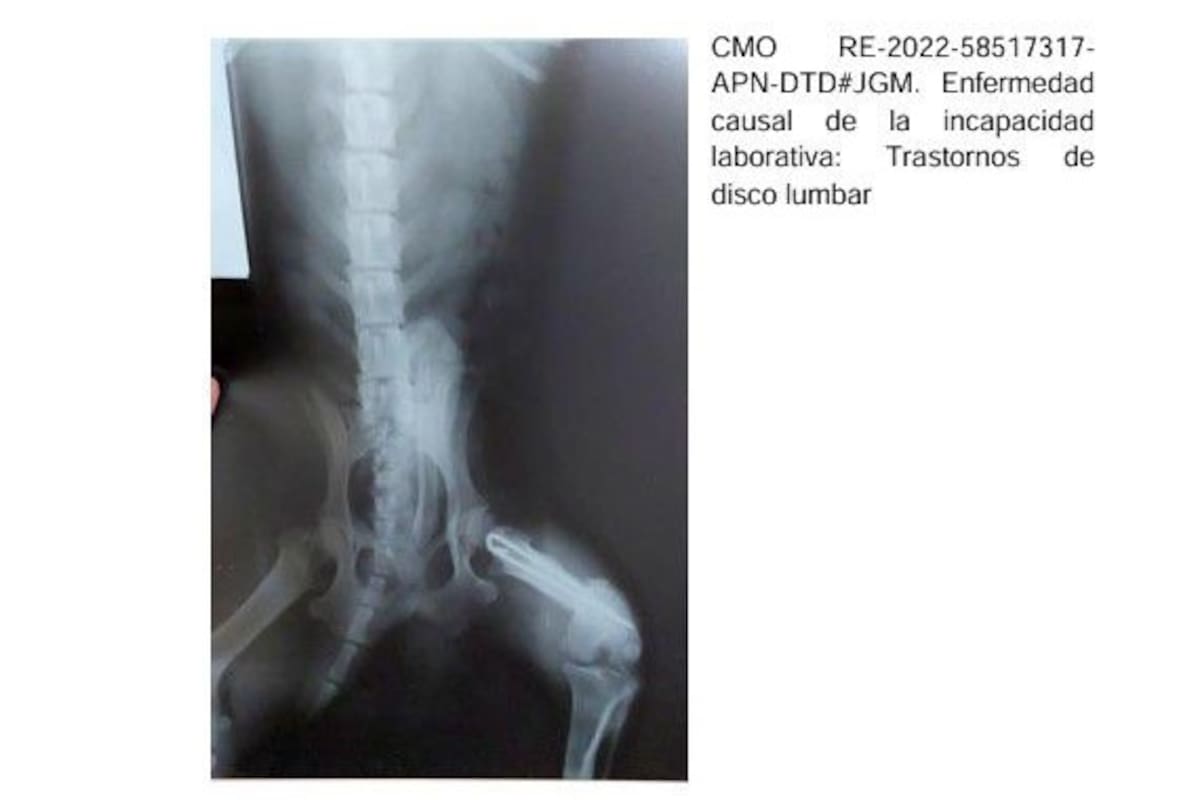

En la muestra auditada de más de 2500 pensiones, la agencia anuló las que habían sido otorgadas irregularmente; incluían expedientes en los que la radiografía de un perro acompañaba el certificado médico por un trastorno de disco lumbar emitido por un médico de Corrientes. En Chaco, con la misma radiografía de hombro se justificaron 150 pensiones por invalidez.